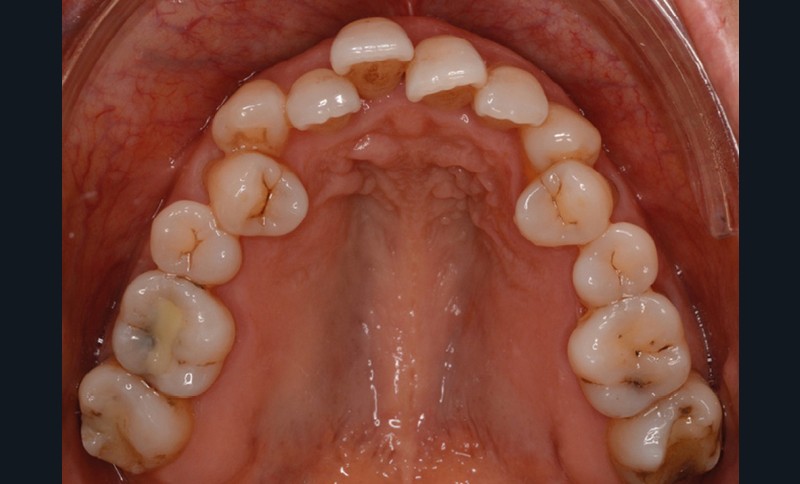

Présentation du cas (fig. 1 à 9)

La patiente présente par ailleurs une parodontite chronique modérée stabilisée (Stade 3, grade C selon la classficaiton de Chicago 2018) et bénéficie d’une maintenance trimestrielle chez son parodontiste, qui nous donne son accord pour le traitement orthodontique moyennant un suivi très régulier.

Sur le plan dentaire, la patiente est en classe III droite et gauche, canine et molaire de 6 mm, avec une occlusion inversée antérieure localisée à 11, 12 et 22. Elle présente une dysharmonie dents-arcades sévère, une agénésie d’une incisive mandibulaire est à signaler, et les troisièmes molaires ont été extraites à l’âge de 21 ans.

Au niveau fonctionnel, on note un bruxisme statique avec contact permanent entre les dents maxillaires et mandibulaires. La patiente présente des prématurités en relation centrée sur les incisives, le guidage en propulsion est perturbé et des interférences multiples sont retrouvées en latéralités droite et gauche.